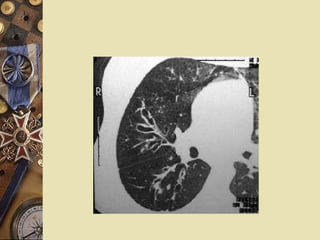

Evaluation CT or HRCT:   high sensitivity and specificity Train track sign:   the bronchial wall is thicken and visible; the bronchi lose the trend of narrowing from proximal end to distal end.

Evaluation CT orHRCT: high sensitivity and specificity Train track sign: the bronchial wall is thicken and visible; the bronchi lose the trend of narrowing from proximal end to distal end.